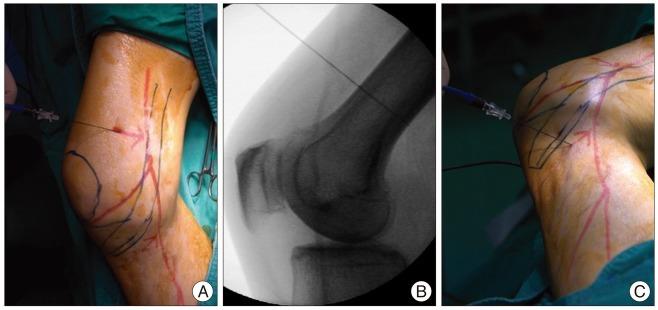

A 65-year-old male presented with pain in his right medial calf. An imaging study revealed no acute lesions, and a diagnosis of saphenous neuralgia was made by a nerve conduction study. He received temporary pain relief with saphenous nerve blocks twice in a one-week interval. Pulsed radiofrequency neuromodulation reduced pain to 10% of the maximal pain intensity. At 6 months after the procedure, the pain intensity was not aggravated even without medication. Pulsed radiofrequency neuromodulation of the saphenous nerve may offer an effective and minimally invasive treatment for patients with saphenous neuralgia who are refractory to conservative management.

一名65岁男性因右小腿内侧疼痛就诊。影像学检查未发现急性病变,经神经传导研究诊断为隐神经痛。他在一周内接受了两次隐神经阻滞,疼痛得到了暂时缓解。脉冲射频神经调节将疼痛减轻至最大疼痛强度的10%。术后6个月,即使未用药,疼痛强度也未加重。对于保守治疗无效的隐神经痛患者,隐神经脉冲射频神经调节可能提供一种有效且微创的治疗方法。